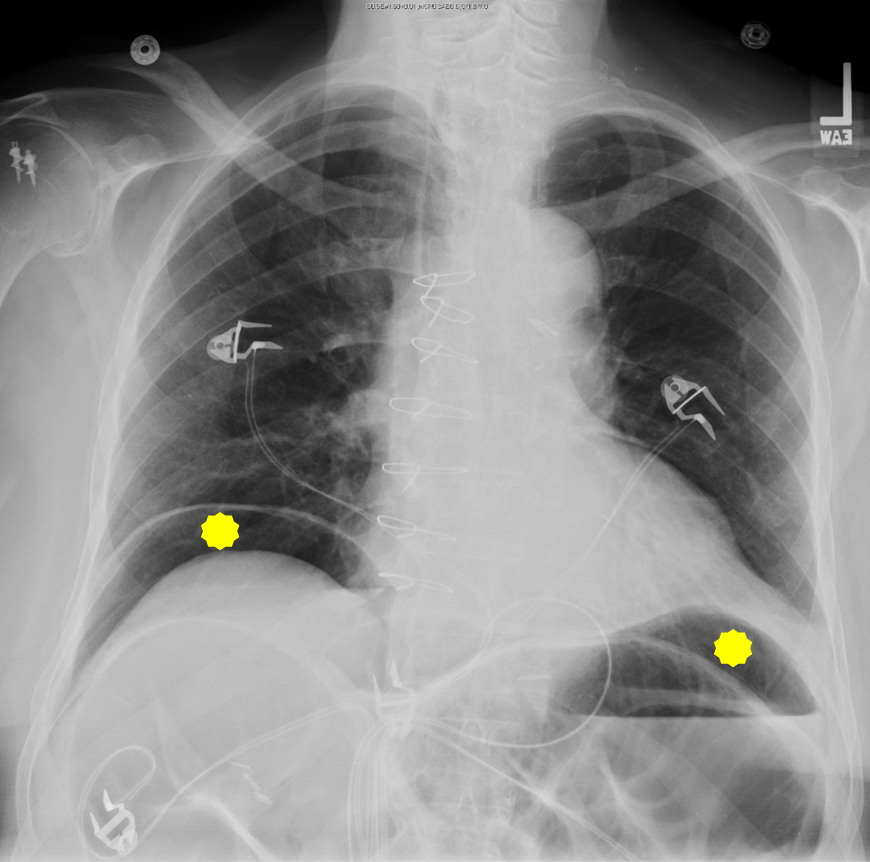

This patient has a large volume of free gas under the diaphragm. This is a sign of bowel perforation. in patients who have small livers (cirrhosis), or flattened diaphragms due to lung hyperexpansion (emphysema), a void is created within the upper. pneumoperitoneum is the presence of air or gas in the abdominal (peritoneal) cavity.

Air In Diaphragm X Ray . This is a sign of bowel perforation. pneumoperitoneum is the presence of air or gas in the abdominal (peritoneal) cavity. This patient has a large volume of free gas under the diaphragm. in patients who have small livers (cirrhosis), or flattened diaphragms due to lung hyperexpansion (emphysema), a void is created within the upper.